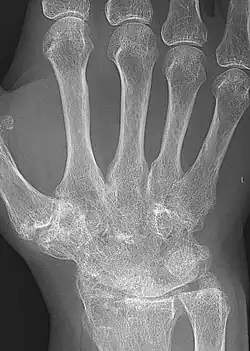

| A hand severely affected by rheumatoid arthritis. This degree of swelling and deformation does not typically occur with current treatment. | |